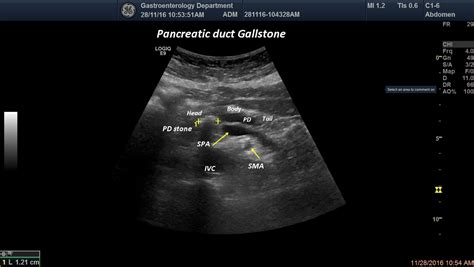

• Pancreatic Stones: Calcifications within the duct can physically obstruct the flow of enzymes, leading to upstream dilation.

• Biliary Issues: Problems in the gallbladder or bile ducts can exert pressure on the pancreatic duct.